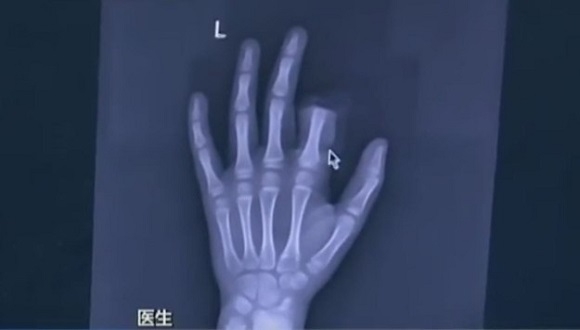

Babasıyla yaptığı tartışmadan sonra kafası oldukça karışmış olmalı ki çocuk, derhal mutfağa yönelip eline bir bıçak alıyor ve sol işaret parmağını kesiyor. Acil bir şekilde hastaneye yetiştirilen çocuk 3 saatlik bir ameliyata alınıyor ancak kopan parmak tekrar yerine yerleştirilemiyor.